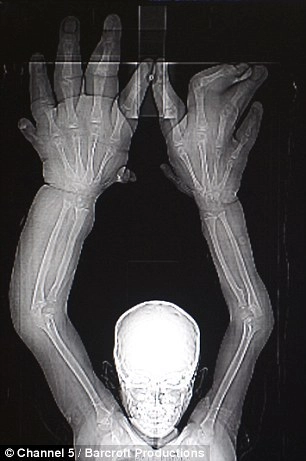

Восьмилетний Калим из Индии не может вести такой же образ жизни, как его сверстники из-за огромных рук весом 16 килограмм. От конца среднего его пальца и до начала ладони — 33 сантиметра.

Однако, после того, как история Калима появилась в заголовках нескольких международных газет, восьмилетнему «хеллбою», наконец, решили помочь медицинские эксперты в южной Индии. Специалисты установили, что проблемы ребенка вызваны макродактилией или локальным гигантизмом, сообщает Daily Mail.

Гигантизм — нейроэндокринное заболевание, характеризующееся чрезмерным увеличением клеточной массы организма и сравнительно пропорциональным увеличением костей скелета, мягких тканей и других органов. Локальный гигантизм, соответственно, характеризуется резким увеличением какой-то одной части тела.

В результате 8-часовой операции, врачам удалось уменьшать объем предплечья и руки. Ряд последующих операций был проведен на пальцах ребенка, что позволило не только сократить их размер, но и добиться остановки дальнейшего роста кисти ребенка.